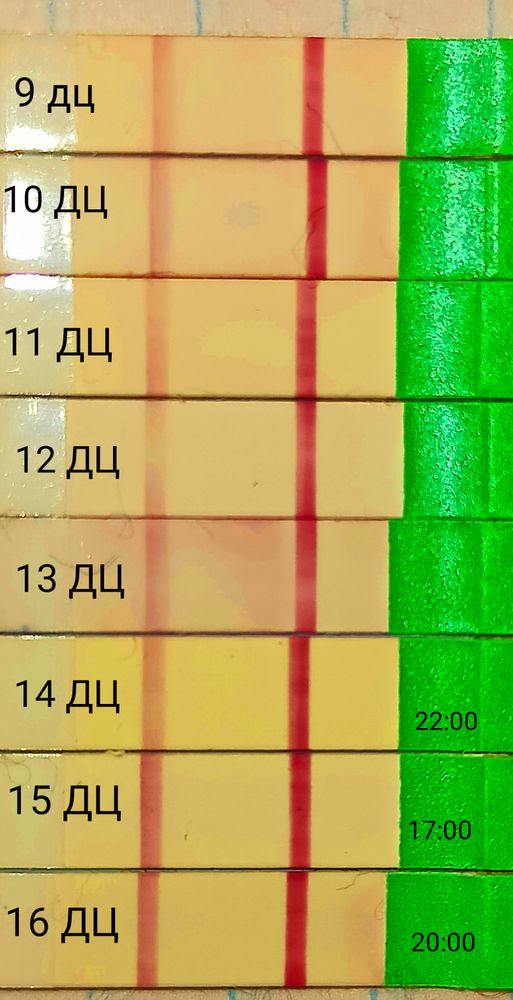

Вот выбрала по одному на каждый день самые яркие:

Я думаю не стоит часто мочить тесты на О, они всегда разные в течении дня, всë равно пик сложно пропустить, мочить лучше один раз вечером с 17:00 до 20:00 и в одно и тоже примерно время, а не как я в разноброс.